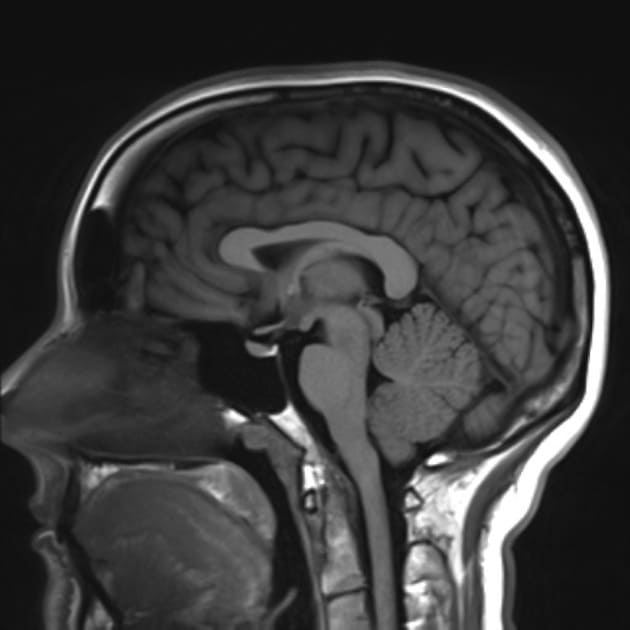

При проведении магнитно-резонансной томографии решающую роль играют присутствующие повсюду в организме атомы водорода. Под воздействием магнитного поля, которое в 20 000 раз мощнее земного, их протоны выстраиваются в определенном направлении. Затем частицы приводятся в движение с помощью радиосигналов. Когда они возвращаются в исходное положение, то выбрасывают накопленную энергию. Производимые МР-сигналы зависят от химического окружения протонов (ликвор, кровь и т. д.) и преобразуются компьютером в объемные послойные изображения в градациях серого.

Сеанс занимает 15–45 минут. Важно, чтобы больной лежал неподвижно, так как от этого зависит качество полученных снимков. Нередко медикам приходится прибегать к седативным средствам. Для увеличения контрастности тканей пациенту вводят специальный препарат.

Магнитно-резонансная томография – также неинвазивный метод диагностики. В его основе – воздействие магнитного поля на организм пациента. Под влиянием этого поля атомы водорода могут менять свое положение. Такие изменения фиксируют датчики МРТ. Они преобразовывают и отцифровывают информацию, которая передается на монитор. В итоге врач-диагност получает серию послойных снимков, где изображен мозг в трехмерном пространстве.

Магнитная томография безвредна, так как использует магнитное поле. Процедура безболезненна и не нуждается в дополнительных манипуляциях (за исключением введения контрастного вещества).

Диагностический метод зарекомендовал себя в исследовании поражений мягких тканей мозга, например, при диагностике геморрагического инсульта. Что может показать магнитно-резонансная томография:

Физическая основа работы магнитно-резонансного аппарата кроется в особенностях взаимодействия магнитного поля и магнитных свойств тканей организма. На томографе благодаря воздействию магнитного резонанса на ядра атомов водорода, которые в определенной концентрации содержатся во всех тканях организма, можно анатомически точно визуализировать состояние органов и тканей. Чем больше обследуемая зона состоит из жидкости, тем ярче и четче получаются ее снимки.

В голове человека есть костные структуры — это череп, есть мягкие ткани — это органы, например глаза, железы, например гипофиз, сосудистая система, которая состоит из артерий, вен и капилляров, серое и белое вещество головного мозга. Поскольку мозг на 80% состоит из воды, на МРТ исследовании все его структуры, кроме черепа, будут прекрасно видны. В костях черепа почти нет воды, а значит процесс ядерного магнитного резонанса очень слабый. Костные ткани лучше всего обследовать с помощью таких рентгенологических методов диагностики, как компьютерная томография или обычный рентген.